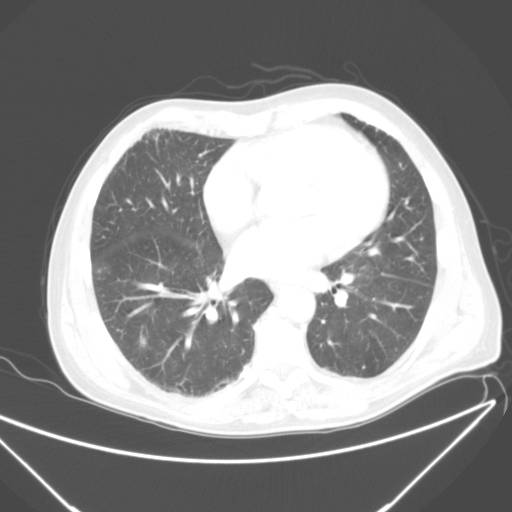

To CT-skanninger af lungerne på samme patient. Først er det øverste billede taget og 6 dage senere tages billedet neden for. Patienten udvikler lungebetændelse, som fremstår som hvide områder i lungerne på billedet neden for (røde pile).